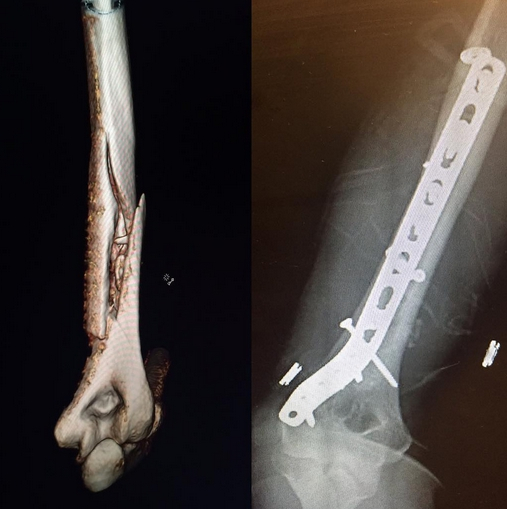

北京时间11月13日消息,美国滑雪女王林赛-沃恩在科罗拉多训练时右手臂骨折,过后接受了手术。

四届世界杯总冠军沃恩在星期四训练时发生意外,右手臂肱骨严重骨折,在当天较晚时动了手术。